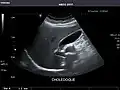

Gallbladder: No stones, wall thickening, or pericholecystic fluid.

Gallbladder -

Gallbladder